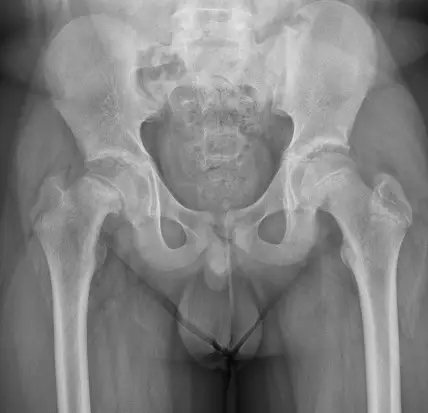

某病人常抱怨右側髖關節疼痛且走路一拐一拐的。門診的 X 光片影像如圖所示,下列敘述何者錯誤? 圖片描述

從病人骨盆髖關節正位 X 光片可見右側股骨近端生長板區域明顯增寬且邊緣不規則(physis widening and irregularity),同時股骨頸相對於股骨頭出現向上、向前的移位(metaphyseal prominence),形成所謂「冰淇淋掉落」徵象。髖關節呈外旋位置,反映 Drehmann’s sign(被動屈髖時出現外旋),這些都是 SCFE 的典型放射線表現(pubmed.ncbi.nlm.nih.gov)。